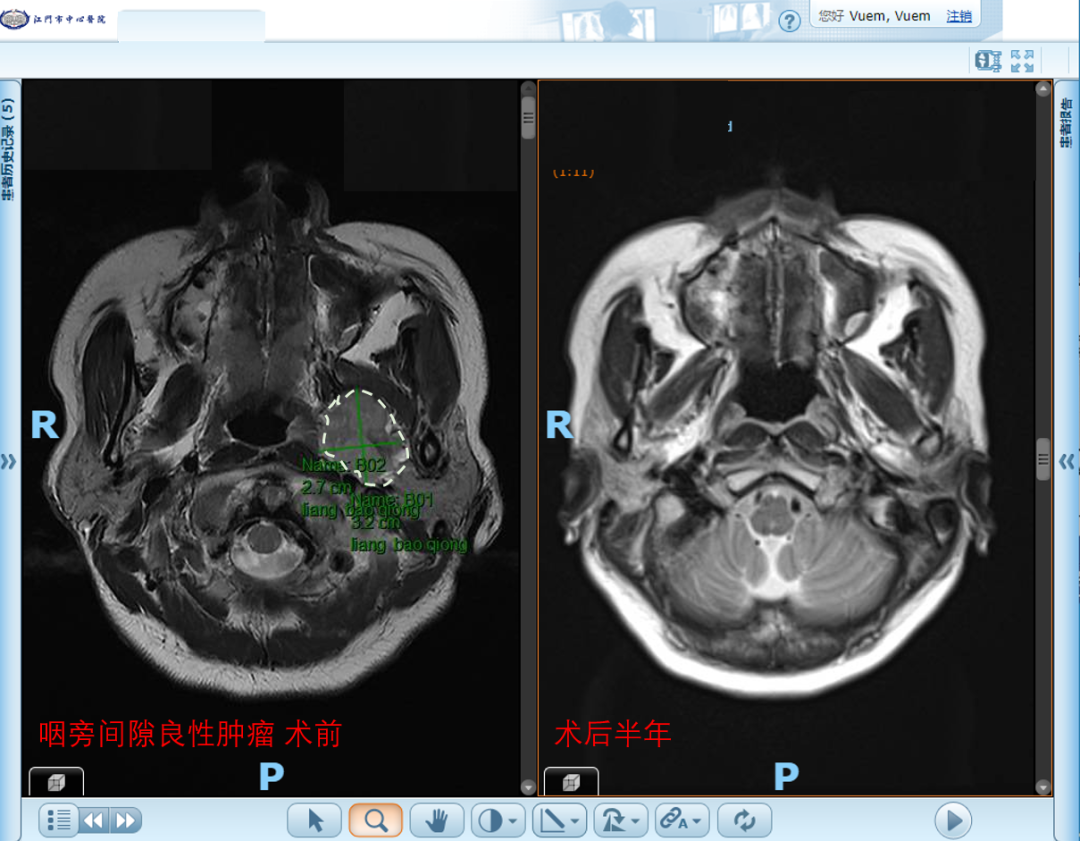

自2023年起,科室在五邑地区率先开展鼻内镜下复发性鼻咽癌切除及带蒂瓣修复术,为复发性鼻咽癌患者提供了优于二程放疗的治疗选择;随后,又陆续独立开展鼻内镜下翼腭窝、颞下窝及中颅窝底肿瘤切除术,进一步拓展了微创手术的技术边界;同期还成功完成五邑地区首例咽后淋巴结清扫术。这一系列技术突破,标志着我院在鼻咽-颅底领域的诊疗能力已达到了区域领先水平,也为复杂疾病患者带来了更为有效的治疗希望。